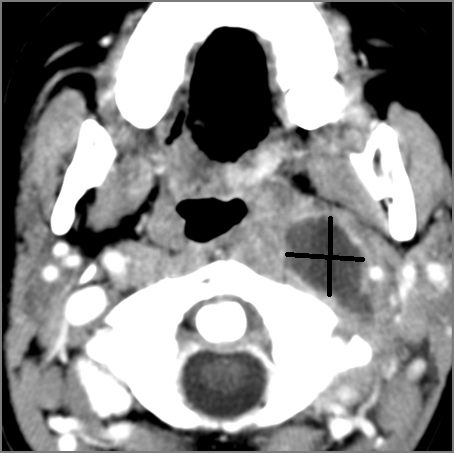

Prevertebral and Epidural Spaces

There is edema/abscess within in the prevertebral or paravertebral spaces. [Yes/No]

There is edema/abscess within in the epidural space. [Yes/No]

There is erosive process involving the disc spaces or other components of the spine. [Yes/No]